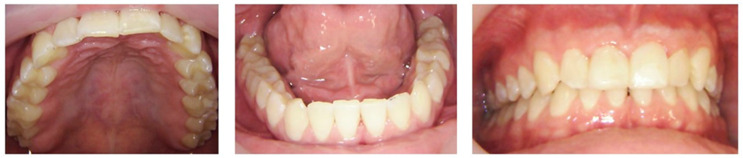

背景:在加拿大,尽管全民医疗保健,但牙科保健仍然主要由私人资助,造成了经济障碍,使许多人无法获得基本服务。这个案例研究是一个更大的倡议的一部分,一个微笑研究项目,该项目评估免费牙科护理对口腔健康和整体福祉的影响,这些人在过去两年中由于经济限制而无法获得牙科服务。该计划的参与者接受必要的牙科护理,并参加后续预约,以评估持续免费护理的长期效果。临床病例:这个混合方法的病例报告集中在一位26岁的男性参与者身上,并将定性的半结构化访谈与临床和自我报告的数据相结合,提供了对他的经历的深入了解。结果:临床结果证明了所提供的牙科治疗的有效性,而自我报告的措施表明改善了口腔健康,对牙齿外观的满意度,增强了心理社会健康,增强了自尊,减少了牙科焦虑,改善了口腔卫生习惯。定性访谈确定了反映该项目积极体验的三个关键主题:入学便利、员工友善和整体幸福感的提高。定量和定性分析的结合表明,在客观和主观措施方面,特别是在总体福祉方面,都取得了重大进展。结论:持续的免费牙科护理有效地解决了参与者的口腔健康和整体福祉,即使在两年的随访中,大多数益处仍在持续。这些个人水平的结果为加拿大医疗保健系统中全民牙科覆盖的潜在优势提供了初步的见解。

Background: In Canada, despite universal healthcare coverage, dental care remains predominantly privately financed, creating financial barriers that prevent many from accessing essential services. This case study is part of a larger initiative, the One Smile Research program, which evaluates the impact of cost-free dental care on the oral health and overall well-being of individuals who have been unable to access dental services in the past two years due to financial constraints. Participants in the program receive necessary dental care and attend follow-up appointments to assess the long-term effects of continuous cost-free care. Clinical Case: This mixed-methods case report focuses on a 26-year-old male participant and integrates a qualitative semi-structured interview with clinical and self-reported data, providing an in-depth understanding of his experiences. Results: Clinical outcomes demonstrated the effectiveness of the provided dental treatments, while self-reported measures indicated improved oral health, satisfaction with dental appearance, enhanced psychosocial well-being, increased self-esteem, reduced dental anxiety, and better oral hygiene habits. The qualitative interview identified three key themes reflecting positive experiences with the program: ease of admission, staff kindness, and overall well-being improvement. The integration of both quantitative and qualitative analyses revealed significant advancements in both objective and subjective measures, particularly regarding overall well-being. Conclusions: The continuity of cost-free dental care effectively addressed the participant's oral health and overall well-being, with most benefits sustained even at the two-year follow-up. These individual-level outcomes offer preliminary insight into the potential advantages of universal dental coverage within the Canadian healthcare system.